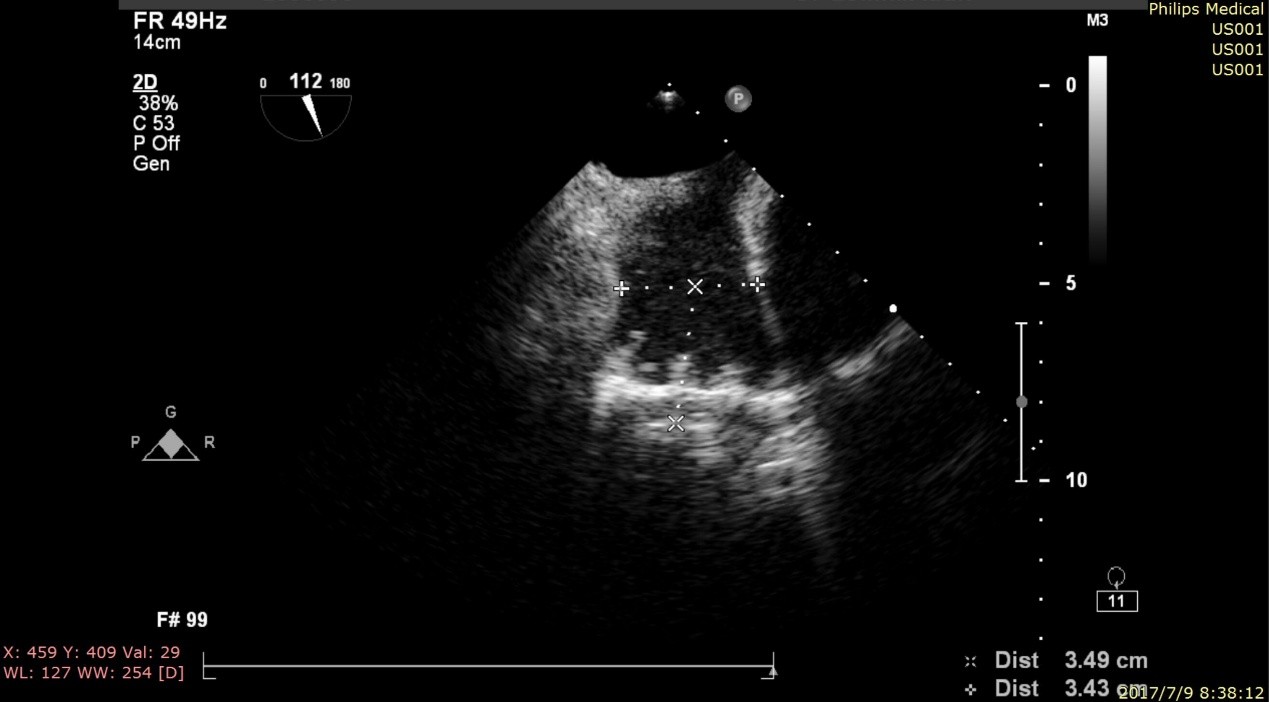

术前TEE评估:

左心耳开口及深度的测量